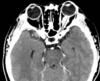

35 anos

Hemangioblastoma